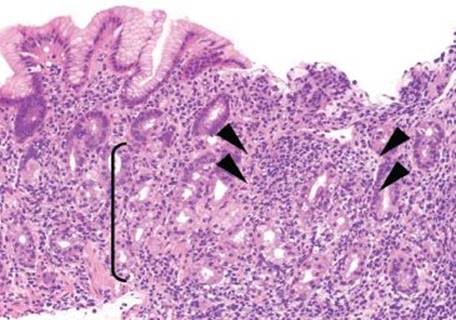

BASAL LYMPHOCYTIC INFILTRATE SUBPATTERN

This subpattern of chronic gastritis is defined by a low-lying lymphocytic infiltrate that expands the lamina propria between the base of the gastric glands and the muscularis mucosae. The prototypical case shows a “band-like” infiltrate hugging the muscularis mucosae at scanning magnification. High-power examination shows admixed plasma cells and occasional eosinophils, but the dominant cell type is lymphocytes (Figs. 2.79, 2.97 and 2.98).

Compartment, Basal Lymphocytic Infiltrate Subpattern

Recognizing the compartment in which this pattern arises can aid in determining the etiology of the chronic gastritis. For example, when found isolated to the gastric body/fundus, the changes are more likely related to AMAG, and further identification of additional AMAG patterns of injury can be helpful. In contrast, involvement limited to the antrum (or mixed antral and oxyntic involvement) suggests the etiology may be related to EMAG; however, identification of other concurrent patterns of injury is necessary.

Figure 2.97 Chronic gastritis pattern, basal lymphocytic infiltrate subpattern, early AMAG. The dominant pattern of injury in this tissue fragment is a low-lying lymphocytic infiltrate that hugs the muscularis mucosae and expands the lamina propria below the base of the glands (arrow). The oxyntic glands (bracket) indicate that the compartment of injury is body/fundus. Further investigation reveals an area of oxyntic gland atrophy (arrowheads), suggesting early AMAG.